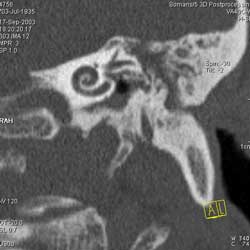

Рис. 10. Принципы КТ высокого разрешения (КТВР) на примере исследования пирамиды височной кости. Применены тонкие срезы (0.5 мм) и "острый" алгоритм реконструкции (кернель 90). (Слева) отчетливо видны элементы внутреннего уха - улитка, полукружные канальцы. (В центре) показана проекция продольного сечения височно-нижнечелюстного сустава. (Справа) - холестеатома.